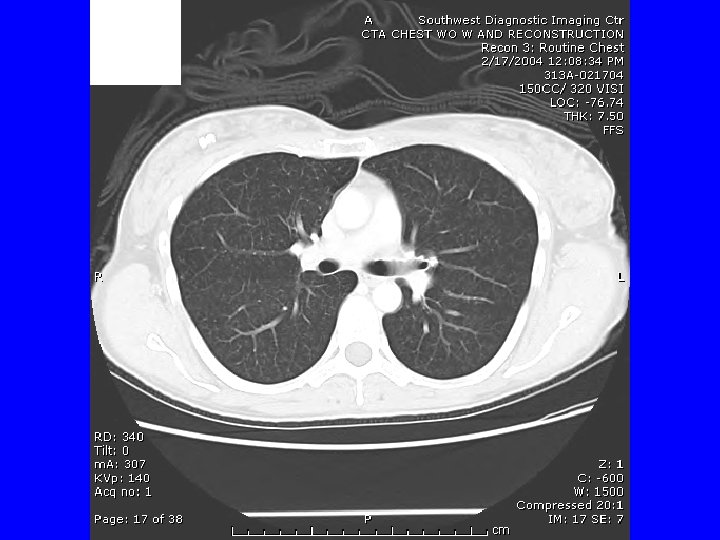

CTA if another episode. She called the next day after a worse episode of tightness, SOB, and hemoptysis. CTA 2/17/04 “tree in bud bilateral and diffuse” suggesting infection or inflammation. Bronchoscopy 2/18/07 appeared normal, with biopsies revealing “mild chronic inflammation. ” March 4 received report of outpatient sputum growing an AFB, and I assumed MAC, and discussed Abx therapy. She then decided on VATS OLBx. (Bronch and OLBx cultures were both negative ultimately. )

HP -CT Findings • • • Ground glass opacities Poorly defined centrilobular nodules Mosaic attenuation on inspiration Air trapping on expiration Reticulation (fibrosis) when chronic Silva CI, Churg A, Muller NL. Hypersensitivity pneumonitis: spectrum of highresolution CT and pathologic findings. Am J Roentgenol 2007; 188: 334 -44.